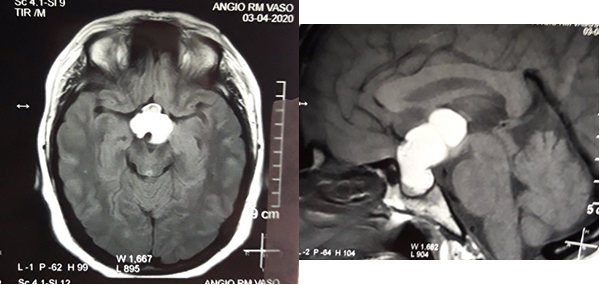

En RM de cerebro se observa lesión espacio ocupante selar-supraselar con aspecto multilobulado que invade cisterna interpeduncular y desplaza estructuras del tercer ventrículo. La misma es hiperintensa espontáneamente en T1 con captación heterogénea de contraste, hiperintensa en T2 (Figura 1). En secuencia de angioresonancia se observa su relación medial respecto a arterias carótidas no comprometiendo las mismas (Figura 2). A partir de éstas imágenes obtenidas en resonador 3 Tesla, en el Departamento de Innovación Tecnológica del Instituto Cardiológico de la Ciudad de Corrientes se realizó un proceso de segmentación de las distintas partes de interés (tumor, arterias, nervios ópticos y globos oculares). Para esto se utilizó el software “Open Source 3D Slicer (versión 4.11)” (Figura 3). Una vez segmentadas las regiones de interés, se realizó, mediante una impresora 3D “MAX” de la empresa Creatbot, un modelo 3D cuyos materiales consistieron en poliácido láctico (PLA) y poliuretano termoplástico (Figuras 4 y 5). Con el mismo, se realizó la planificación del abordaje quirúrgico.

Figura 1: RM en secuencia T1 cortes a) 1axial, se observa lesión espontáneamente hiperintensa y su relación con vasos del polígono de Willis. b) RM en secuencia T1 corte sagital, donde se observa extensión supraselar de la lesión comprimiendo lamina terminalis